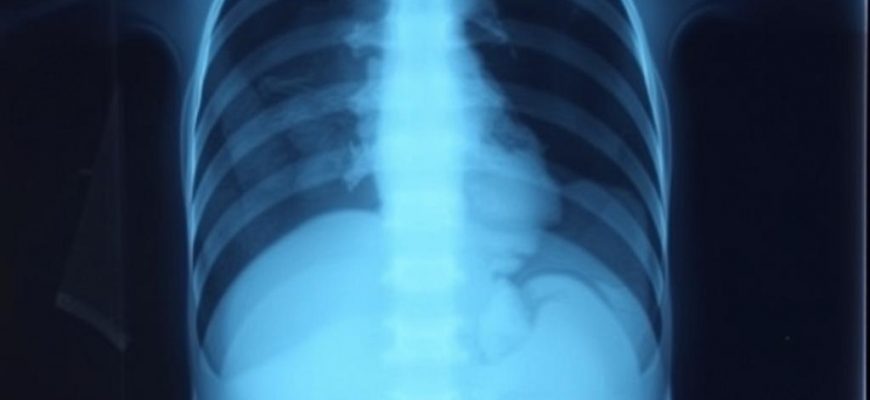

Сегодня разберем, как помогает рентген брюшной полости у детей, как подготовить ребенка и чего ждать на месте. В статье дадим понятные шаги и реальные примеры. Если нужен прием и диагностика в один день, это решают в СМ-Клиника https://www.smdoctor.ru/diagnosis/rentgen/rentgen-bryushnoy-polosti/.

Рентген помогает врачу увидеть, что происходит в животе, когда требуется быстрый ответ. Снимок показывает:

уровень газов и жидкости при кишечной непроходимости

признаки перфорации полого органа по свободному газу под диафрагмой

крупные и средние инородные тела, например монеты, батарейки, детали игрушек

плотные камни, чаще в почках и мочеточниках

выраженный каловый застой при запоре

Также рентген помогает понять, нужен ли срочный хирург, УЗИ, КТ или наблюдение.